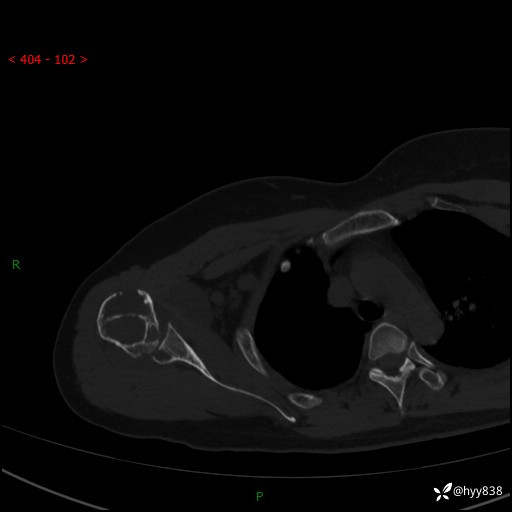

右肩关节CT平扫